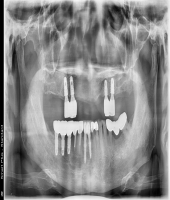

| ● 진료과목 : [임플란트] 틀니 사용중, 임플란트로 교체하기

| ● 내용 : 하악틀니 사용 중 불편감으로 임플란트로 교체한 예 |